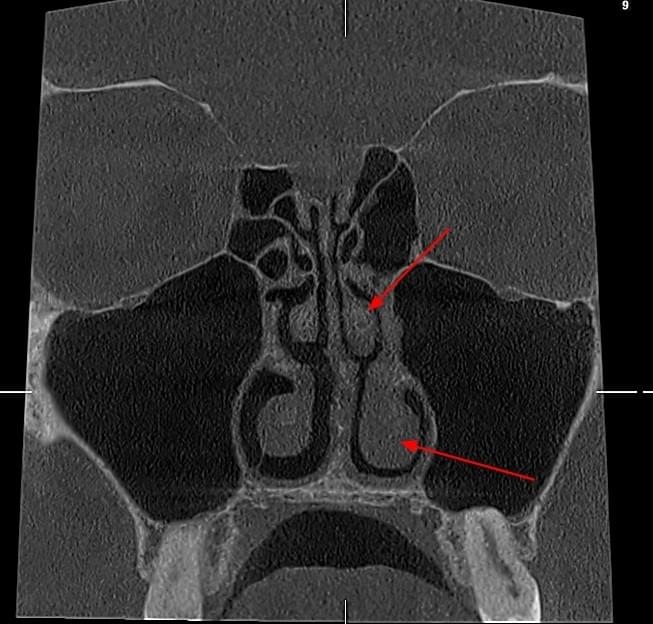

Діагностика гайморових пазух за допомогою КТ

У сучасній медицині КТ придаткових пазух носа (або КТ синусів) — це «золотий стандарт»

діагностики для ЛОР-лікарів та щелепно-лицевих хірургів. Звичайний рентген часто не

показує повну картину, а МРТ не завжди доступний і дорожчий. Комп’ютерна томографія дає

детальну 3D-модель усіх пазух (гайморових, лобних, клиновидних та решітчастого

лабіринту) за 10 секунд і з мінімальною дозою опромінення.

КПКТ (конусно-променева комп’ютерна томографія) — це 3D-знімок високої роздільної здатності. На відміну від звичайного рентгену, КТ показує: